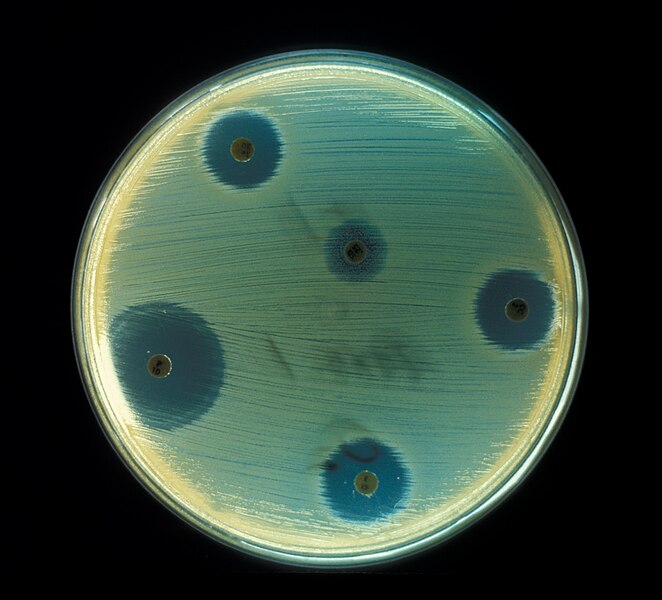

2 – Diagnostic Tools – Spirometry, Arterial Blood gas, Oximeter, Exercise Tolerance Testing, X-ray, Bronchoscopy, Culture and Sensitivity Tests, Sneezing Reflex, Coughing Reflex,